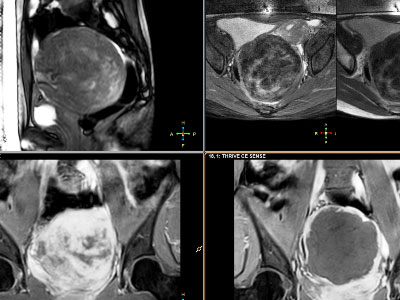

Suy thận